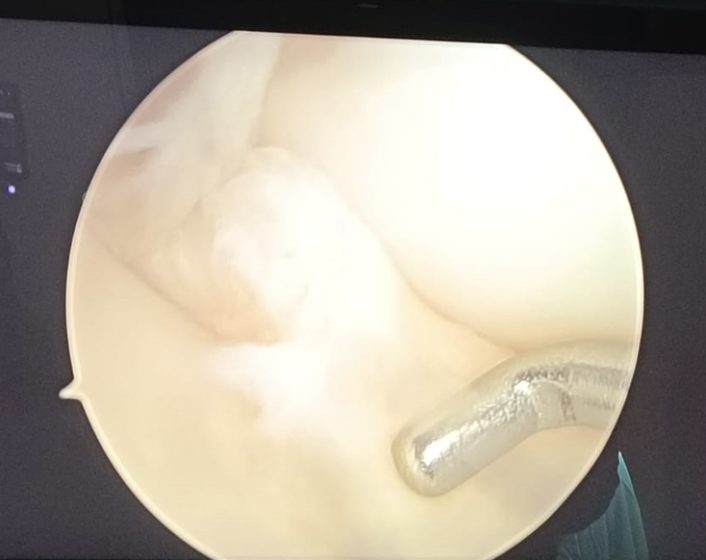

ACL Ligament after Surgery

ACL (Anterior Cruciate Ligament) injury treatment varies based on the injury’s severity and the patient’s lifestyle. For minor tears, non-surgical treatments like rest, physical therapy, and bracing and some times internal bracing may suffice to restore knee stability and function. Physical therapy focuses on strengthening the muscles around the knee, improving flexibility, and regaining balance. For severe tears or active individuals, surgical reconstruction is often necessary. The surgery involves replacing the damaged ligament with a graft, typically from the patient’s own tissue. Post-surgery rehabilitation is critical, involving a structured physical therapy program to ensure proper healing, restore full range of motion, and regain strength.